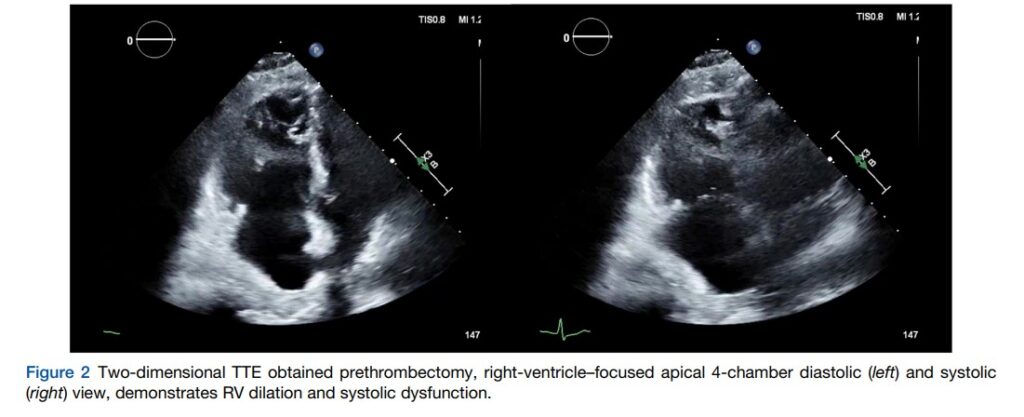

A tomografia também mostrou dilatação do VD e retificação do septo interventricular. Já o ecocardiograma evidenciou, além da dilatação do VD, uma redução moderada a importante da função sistólica pela análise subjetiva.

A pressão sistólica da artéria pulmonar (PSAP) foi estimada em 43 mmHg. Ainda, havia regurgitação tricúspide moderada. Um trombo em trânsito foi aventado pela presença de uma imagem ecogênica móvel observada no aparato subvalvar tricúspide.